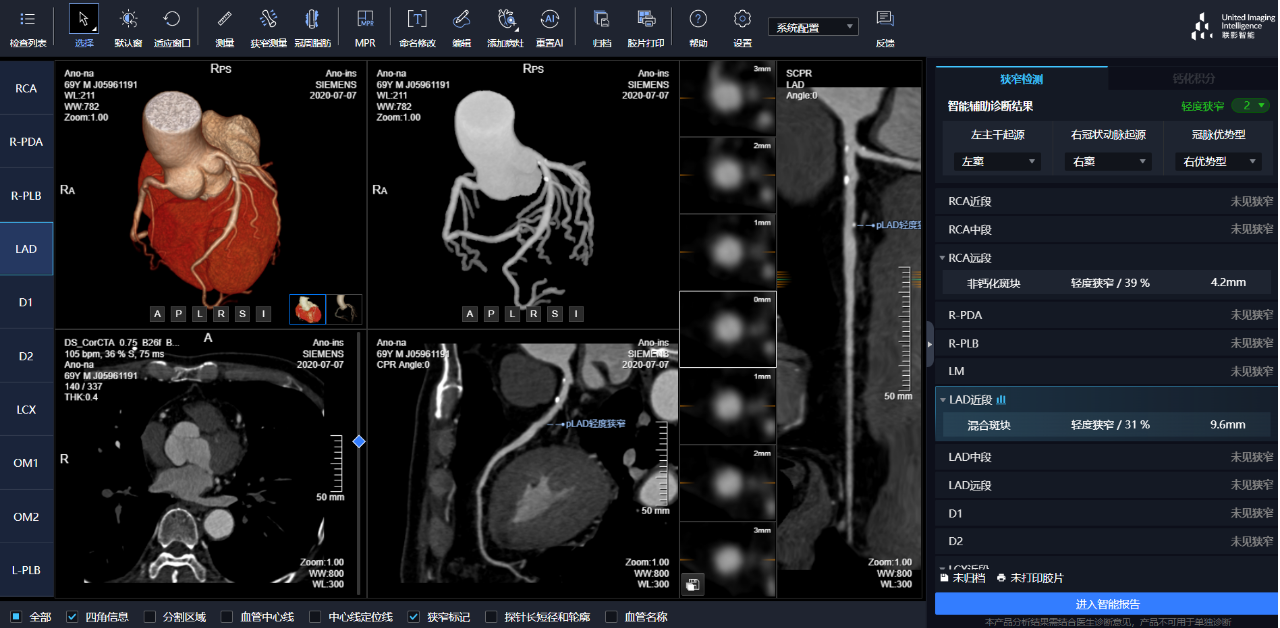

相較于傳統(tǒng)人工閱片,在聯(lián)影智能AI軟件的輔助下,640CT閱片的靈敏度和閱片效率均有顯著提升,對于細(xì)微骨折乃至于隱匿性骨折的判斷,準(zhǔn)確度更高,極大地減少了漏診及誤診。

通過3D視圖可任意旋轉(zhuǎn)觀看血管全貌,AI秒級實(shí)時(shí)計(jì)算重建血管,可實(shí)現(xiàn)多維輔診包含:板塊定性定量分析、狹窄評估、心肌橋檢出、支架檢出、鈣化積分,全程AI關(guān)注心血管健康。